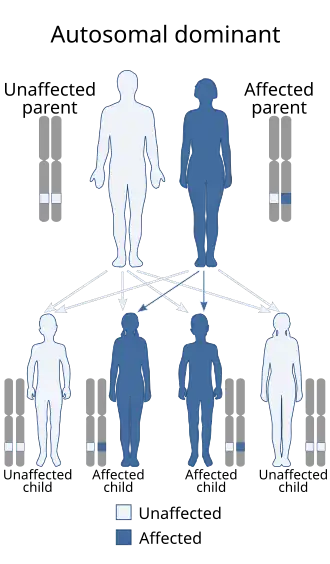

Genética

Algumas anomalias genéticas podem também causar cancro do endométrio. As causas genéticas contribuem para 2 a 10% do total de casos da doença.[3][24] A síndrome de Lynch, uma doença genética autossómica dominante que causa principalmente cancro colorretal, pode também causar cancro do endométrio, principalmente antes da menopausa. As mulheres com síndrome de Lynch têm um risco de 40 a 60% de desenvolver cancro do endométrio.[17] 20% destas mulheres desenvolvem simultaneamente cancro do endométrio e cancro do ovário. Em quase todos os casos, o cancro do endométrio desenvolve-se primeiro, em média 11 anos antes.[18] A carcinogénese na síndrome de Lynch tem origem numa mutação dos genes MLH1 e/ou MLH2, os quais são responsáveis pela correcção de erros no ADN. As mulheres com síndrome de Lynch correspondem a entre 2 a 5% dos casos de cancro do endométrio.[21] O risco varia de acordo com o gene mutado. Em mutações do gene MLH1, o risco é de 54%; do gene MSH2 21%; e do gene MSH6, 16%.[25]

As mulheres com historial na família de cancro do endométrio apresentam risco acrescido.[9] Os dois genes frequentemente associados com outros cancros em mulheres, o BRCA1 e o BRCA2, não causam cancro do endométrio. Embora exista uma aparente ligação com estes genes, pode-se atribuir esta ligação ao uso de tamoxifeno nos cancros da mama e do ovário, um fármaco que aumenta o risco de cancro do endométrio.[17] A síndrome de Cowden, uma condição genética hereditária, pode também aumentar o risco de cancro do endométrio. As mulheres com esta condição apresentam um risco de entre 5 a 10% de desenvolver a doença ao longo da vida,[3] em comparação com um risco de 2 a 3% entre mulheres não afectadas.[18]